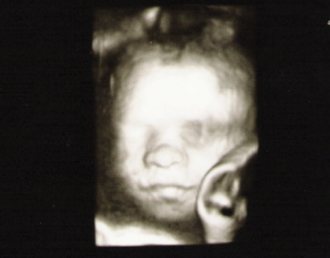

Erstes CTG - Tagebücher aus der Schwangerschaft von Ingrid aus Hürth